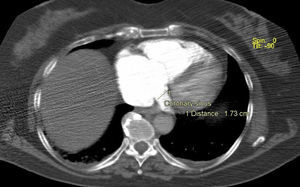

Para além da avaliação da carga embólica na TCMD, foram efetuadas medições quantitativas dos diâmetros das estruturas vasculares (VCS e VA) e cardíacas (VD, VE, ratio VD/VE; SC, AP, Ao, ratio Ap/Ao) relacionadas com a árvore pulmonar. O desvio do SIV e o refluxo de contraste na veia cava inferior (VCI) foram avaliados qualitativamente, de forma a definir os sinais de DVD (Figuras 2-5).

Na angio-TC, o grupo B apresentou diâmetros do VD, ratio VD/VE (p-0,002), VCS, VA e SC superiores. Os diâmetros da AP e o ratio AP/aorta foram semelhantes.

A percentagem de sobrecarga no septo IV e refluxo na VC inferior (p-0,001) foram superiores no GB, revelando-se o QS > 18 pontos, preditor independente de DVD (VD/VE > 1) (OR:10,85 [CI 3,20-36,77]; p<0,001) (AUC ROC: 0,79; p<0,001) com uma sensibilidade estimada em 78,4% e especificidade em 79% (Figura 1, Tabela 7).

Na angio-TC, o QS correlacionou-se linearmente com os parâmetros de DVD avaliados (diâmetros do VD, VCS, VA e SC; ratio VD/VE e AP/Ao; percentagem de sobrecarga no SIV e de refluxo na VCI), conferindo à carga embólica avaliada por QS um potencial multiparâmetros que ainda não se encontrava descrito na literatura.